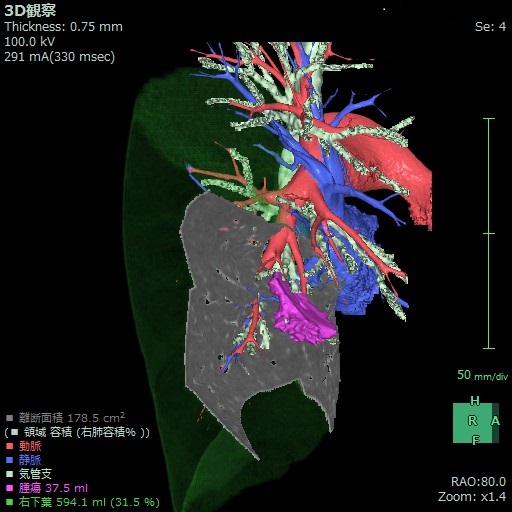

肺葉切除術よりも肺機能をたくさん残せるメリットがありますが、手術操作が細かくなり難易度は少し上がります。高齢者の増加と早期肺がんに対する縮小手術の適応拡大で今後ますます増えてくる術式です。当科では複数の区域を同時に切除する術式や、亜区域切除術など更に複雑で難しい手術も完全胸腔鏡下で多数行っています。肺葉切除術に比べると手術時間が少しだけ長くなりますが傷の大きさは同じです。2016年からは赤外光を照射できる特殊な5mmの胸腔鏡とインドシアニングリーン(ICG)という検査で使う色素を用いて区域間を明瞭に描出しながら手術を行っています。術前に作成した肺動静脈や気管支の詳細な3D画像を手術中に確認しながら、最先端の方法を駆使して複雑な手術も安全確実にできるようになっています。

開院以来、肺癌手術の95%が胸腔鏡を使用して行われています。もっとも多い術式は胸腔鏡下肺区域切除術です。また気管支形成術や血管形成術などの難しい手技が必要な場合でも胸腔鏡による手術が行われています。当科ではCT画像を基に術前に肺動静脈や気管支の立体画像を作成して、手術方法の検討や手術のシミュレーション、術中ナビゲーションに活用し、安全確実に手術を行うように努めています。